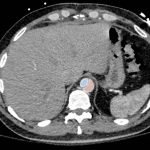

Chest x-ray and CT angiogram was performed to evaluate his thoracic and abdominal vasculature. Chest x-ray did not show any significant widening of the mediastinum. The CT angiogram demonstrated an intimal tear along the aortic arch separating a true and false aortic lumen, consistent with an acute aortic dissection. The true lumen (highlighted in blue in images 1-5) can be identified by continuity with an undissected part of the aorta1. While the false lumen (highlighted in red in images 1-5) can be identified by its crescent shape and larger cross-sectional area.1